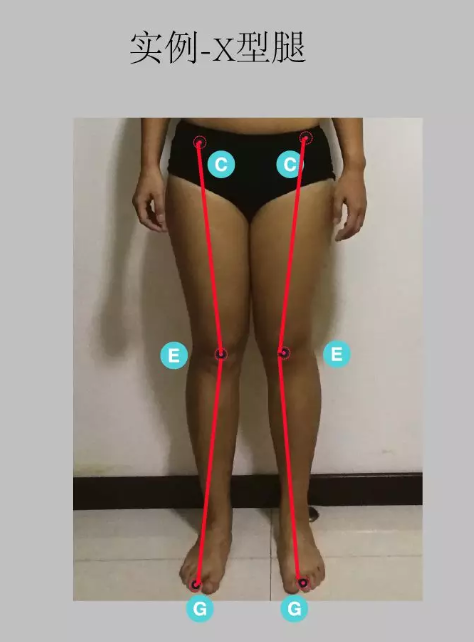

X 型腿:观察髂前上棘、髌骨和第二 脚趾 头是否在一直线,如下图所示,在髌骨处形成一个夹角,则为 X 型腿; 这个角度若是反方向,则为膝关节内翻造成的 O 型腿。